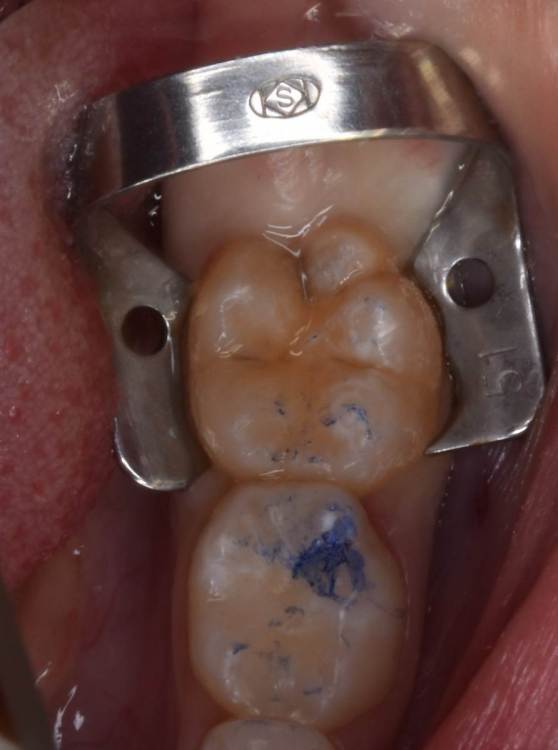

CRAZYDUCK Опубликовано 21 июля, 2022 Автор Поделиться Опубликовано 21 июля, 2022 Герметизация фиссур . Метод профилактики кариеса . В большинстве случаев для первых постоянных моляров . Прорезывание этих зубов часто проходит незаметно для родителей . Если проводить герметизацию , то с изоляцией и предварительной бережной очисткой от налёта . Как наладить гигиену у детей , как довести ее до идеала ? Я не знаююююююююю!!!!!! ??? Детям это не нужно , родители надеются на ответственность детей ( типа ты же уже большой / большая ). Но ! Обращаясь к родителям хочу сказать - примите этот факт , дети ещё не обладают достаточным уровнем ответсвенности . Участь детских стоматологов и гигиенистов - повторение мать учения , капля камень долбит не битьем , а частым падением . Режим спокойного попугая активирован . Рассказать , показать , записать на видео процесс качественной чистки зубов в стенах клиники и отправить это видео родителям для домашнего контроля . 4 1 Ссылка на комментарий